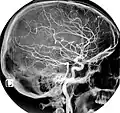

As artérias carótidas primitivas ou comuns esquerda e direita são responsáveis por fornecer o sangue a toda a região da cabeça.[1] A artéria carótida primitiva direita origina-se do tronco arterial braquiocefálico, enquanto a carótida primitiva esquerda origina-se directamente do arco aórtico. Cada uma das carótidas primitivas dá origem a uma artéria carótida externa e uma artéria carótida interna.[1]

Na parte inferior do pescoço, as duas artérias carótidas comuns são separadas uma da outra por um intervalo muito estreito que contém a traqueia; mas na parte superior, a glândula tireoide, a laringe e a faringe separam as duas artérias. Apesar de ambos os ramos viajarem para cima, a artéria carótida interna segue um caminho mais profundo (mais interno), eventualmente adentrando o crânio para fornecer sangue ao cérebro.

A artéria carótida externa viaja mais superficialmente e emite numerosos ramos que fornecem sangue ao pescoço e rosto.